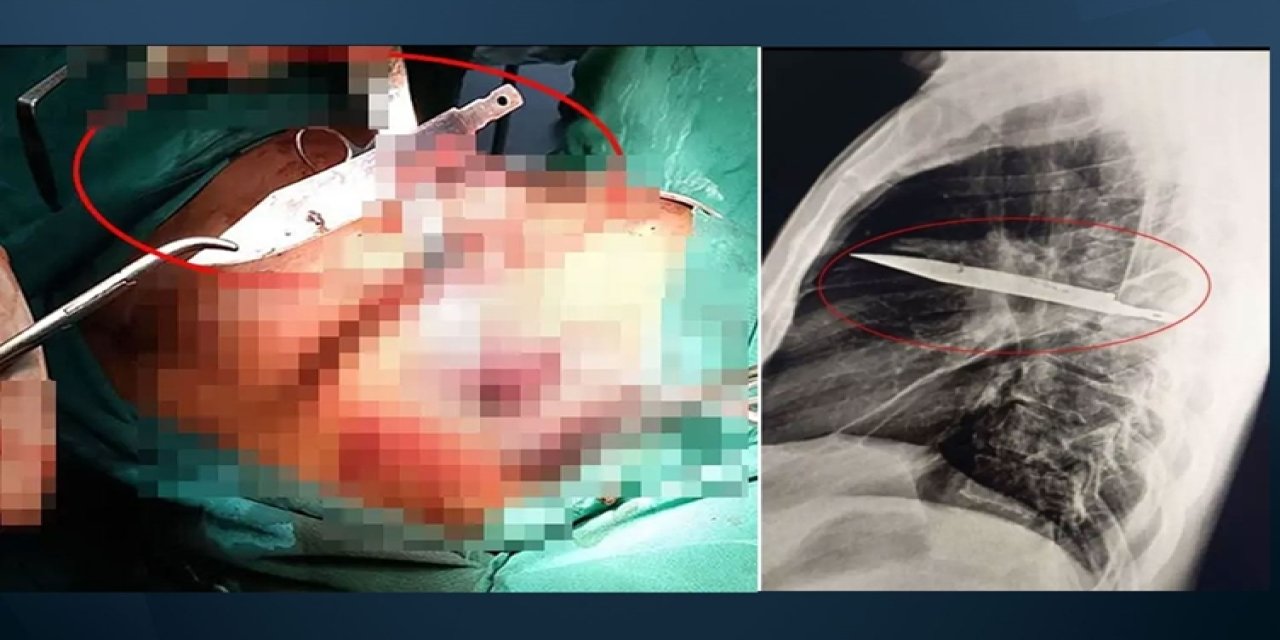

Ağrıyla gitti: 8 yıldır göğsünde bıçakla yaşadığını öğrendi